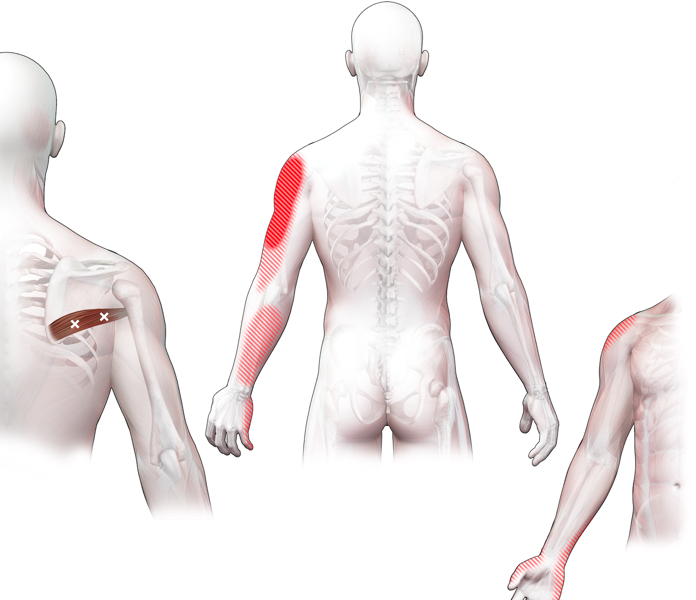

Spieren (Nederlands)

Spieren (nederlands)

Spieren (Latijn)

Spieren (latijn)